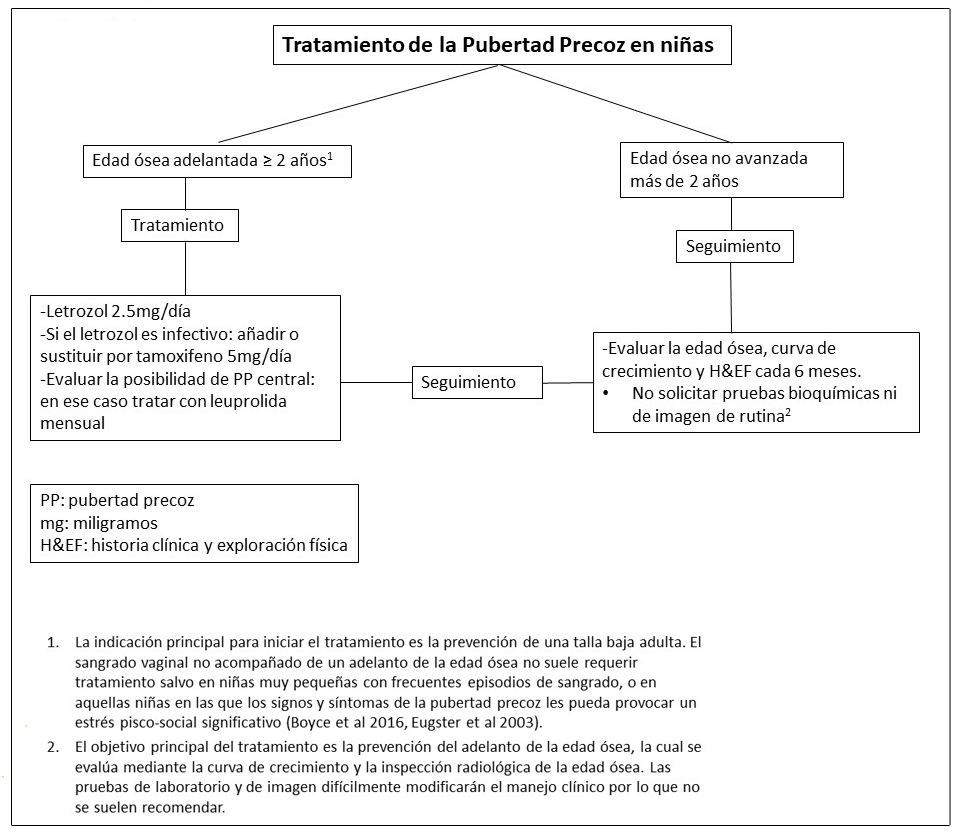

Tabla 4. Tratamiento de Endocrinopatías en individuos con Displasia Fibrosa/Síndrome de McCune-Albight

- Ver Figura 13. La pubertad precoz no es frecuente en varones.

- Boyce et al 2012a.

- Dada la exposición prematura a esteroides sexuales (ver Descripción Clínica), la pubertad precoz central puede presentarse a pesar de que el/la niño/a tuvieran un buen control de la pubertad precoz periférica.

Figura 13. Manejo clínico recomendado para niños con alteraciones gonadales con Displasia Fibrosa/Síndrome de McCune-Albright